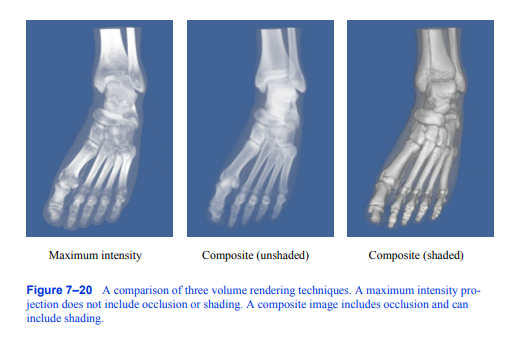

光照有几个优点,通常可以证明图像中额外的复杂性是合理的。首先,考虑到体绘制是一个从3D数据创建2D图像的过程。查看该数据的人希望能够从该图像中了解体积的3D结构。当然,如果你看一张骨骼的照片,从2D表示中很容易理解它的结构。你从图片中得到的两个主要线索是遮挡和灯光效果。如果你看一段骨架的视频,你会得到运动视差的额外线索。显示最大强度投影的静态图像不包括遮挡或照明效果,因此很难理解结构。用合成技术生成的图像确实包括遮挡和合成射线

图7-20三种体绘制技术的比较。最大强度投影不包括遮挡或阴影。合成图像包括遮挡,也可以包括阴影。

函数也可以修改为包含底纹。这三种方法的对比如图7 - 20所示,用于人体足部的CT扫描。为了准确地捕捉照明效果,我们可以使用传输理论照明模型[Krueger91],该模型通过沿着光线的路径积分来描述到达像素的光强度: